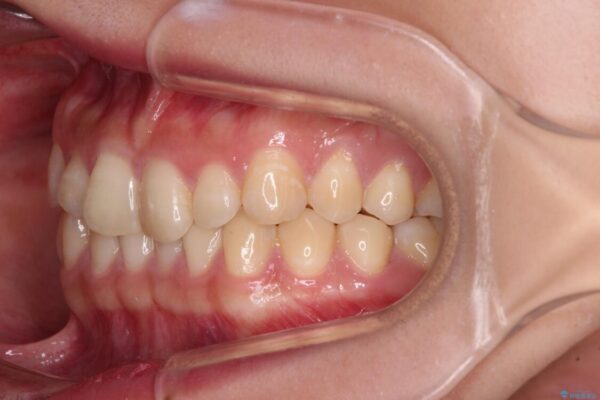

治療前

• 治療途中の奥歯と矯正治療の後戻り インビザライン・ライトによる矯正治療 治療前画像